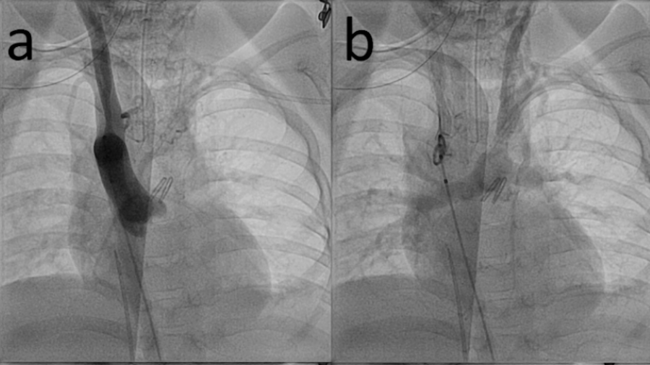

Aortic angiography showed a right aortic arch with only right carotid and right subclavian arteries and retrograde filling of the left carotid, left subclavian artery, and pulmonary arteries (Figure A/B, Video 1). Angiography of the left subclavian artery showed the tortuous, stenotic arterial connection between the pulmonary arteries and left subclavian artery (Figure C, Video 2). After stent placement, there was marked improvement in the caliber of the vessel and systemic saturations (Figure 1D, Video 3). Cerebral NIRS monitoring was used during the procedure with no change after stent placement. She has maintained reasonable saturations and has been seizure-free for over 3 years without neurologic deterioration or further cardiac intervention.